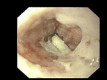

Zollinger-Ellison syndrome is an often progressive, persistent and frequently life-threatening disease, described for the first time as characterized by ulceration of the upper jejunum, hypersecretion of gastric acid and non-beta islet cell tumors of the pancreas; this syndrome is due to the hypersecretion of gastrin. We report a case of Zollinger-Ellison syndrome presenting as severe esophagitis evolving in stenosis, which demonstrates how a delayed diagnosis may induce risk of disease spreading. In this setting new diagnostic approaches, such as somatostatin receptor scanning and positron emission tomography with 68 Ga-labeled octreotide, could be particularly useful, as well as further new therapeutic options, such as molecular targeted treatments and peptide receptor radionuclide therapy, though surgery is currently the only form of curative treatment, and the role of the therapeutic options mentioned needs to be clarified by forthcoming studies.